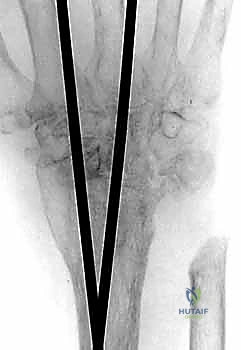

5. التثبيت بالشريحة والمسامير (Plate Fixation)

يتم استخدام شريحة معدنية خاصة (Wrist Fusion Plate)، غالباً مصنوعة من التيتانيوم، مصممة خصيصاً لتناسب تشريح الرسغ. يتم تثبيت هذه الشريحة بمسامير قوية تمتد من عظم الكعبرة في الساعد، مروراً بعظام الرسغ، وصولاً إلى العظم المشطي الثالث (Third Metacarpal) في اليد. هذا التثبيت الصلب يمنع أي حركة ويسمح للعظام بالالتحام لتكوين كتلة واحدة صلبة.

6. الإغلاق (Closure)

بعد التأكد من قوة التثبيت باستخدام جهاز الأشعة السينية داخل غرفة العمليات (C-arm)، يتم إعادة الأوتار إلى مكانها، وإغلاق الشق الجراحي بغرز تجميلية دقيقة لتقليل الندبات، ثم يتم وضع اليد في جبيرة أو دعامة صلبة لحمايتها.